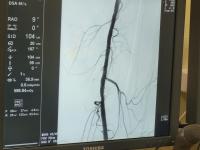

В Региональный сосудистый центр Коломенской больницы с сильными болями в ноге поступил 71-летний житель Зарайска. Врачи диагностировали критическую ишемию, состояние начинающейся гангрены, угрожающее ампутацией единственной ноги – ранее пациент потерял другую конечность из-за атеросклероза. В экстренном порядке через прокол в запястье пациенту выполнили ангиографию, которая подтвердила тяжелое поражение сосудов атеросклерозом, сужения артерий вплоть до их полной закупорки на всем протяжении – от тазобедренного до коленного сустава.

За восстановление кровотока в нижней конечности принялась мультидисциплинарная бригада врачей: сосудистые и рентгеноэндоваскулярные хирурги, анестезиолог-реаниматолог. На первом этапе врачи под рентгеновским контролем выполнили ангиопластику подвздошной артерии – через небольшой прокол в бедренной артерии ввели специальный баллон и с его помощью расправили все сужения. Затем хирурги выполнили бедренно-подколенное шунтирование – наладили кровоток ниже по ходу сосудов. При подготовке бедренной артерии специалисты удалили массивную атеросклеротическую бляшку, преграждающую путь кровотоку. Затем в обход закупоренного участка провели шунт и вшили его в неповрежденный атеросклерозом участок подколенной артерии, таким образом пустив кровоснабжение в обход пораженной артерии. Ангиография показала, что шунт выполняет свою функцию, кровоток в ноге полностью восстановлен на всех уровнях. Таким образом, все вмешательство было выполнено через два небольших разреза, без объемного доступа через брюшную полость и применения наркоза.

«Золотым стандартом диагностики сердечно-сосудистых заболеваний является ангиография, дающая полную картину состояния сосудов. Данное исследование выполняется в рентгеноперационной через небольшой прокол в области запястья пациента. Большинству пациентов, поступающих в отделение сердечно-сосудистой хирургии с острой патологией, назначается данное исследование. По его результатам, непосредственно в операционной, мультидисциплинарная бригада определяет тактику лечения – делает выбор в пользу открытого хирургического, эндоваскулярного или гибридного вмешательства. Эндоваскулярное лечение чаще всего выполняется сразу же – через дополнительные проколы», – пояснил заведующий отделением рентгенэндоваскулярных методов диагностики и лечения Регионального сосудистого центра Виктор Григорьев.